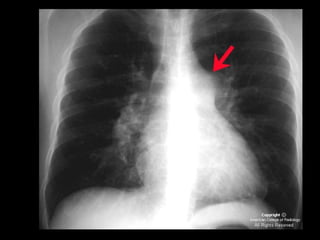

Exames de imagem: Rx Tórax

Primeiro passo na investigação radiológica da

suspeita de HAP;

Achados típicos: aumento do calibre das artérias

centrais, com rápido afilamento dos vasos à medida

que progridem para a periferia;

A área cardíaca pode estar aumentada ou normal;

Calcificação vascular: associado a alta RVP;

Sensibilidade baixa;

Útil para afastar ou sugerir causas de HAP;

Radiografia de tórax normal

HAPI: imagem: Rx e TC

Aumento do calibre dos vasos pulmonares;

Afilamento dos vasos e oligoemia;

Sinais de cardiomegalia direita;